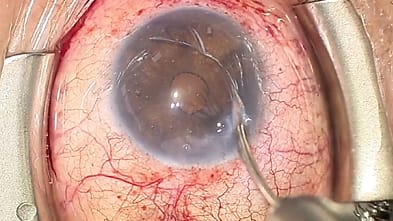

Laser-Titratable Shunt Shows Promise in Feasibility Study

March 19, 2025